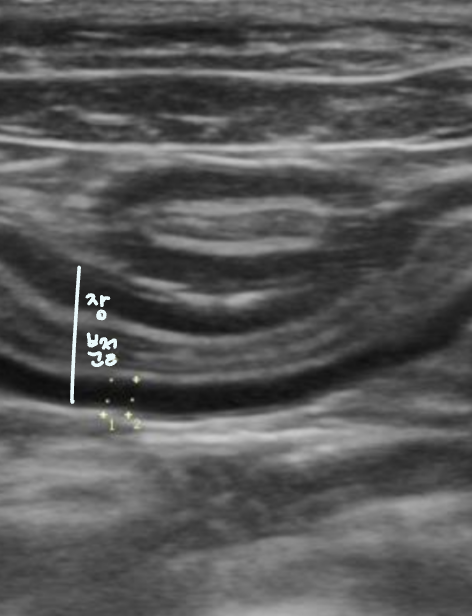

์ ์ ๊ตฌ์กฐ ๊ด์ฐฐ

โ ์ฅ์ ๋จ๋ฉด (๋ฒฝ ๊ตฌ์กฐ ๊ตฌ๋ถ)

- ์์ชฝ๋ฉด๋ถํฐ 4์ธต์ ๊ตฌ์กฐ๋ก ์ด๋ฃจ์ด์ง.

- ์ ๋ง์ธต | Mucosa (์ ์์ฝ์ฑ, ์ด๋์)

- ์ ๋งํ์ธต | Submucosa (๊ณ ์์ฝ์ฑ, ๋ฐ์) โ ๊ฒฐํฉ์กฐ์ง, ๋ฐ์ฌ๊ฐ ๊ฐํด hyperechoic

- ๊ทผ์ก์ธต | Muscularis (์ ์์ฝ์ฑ,์ด๋์)

- ์ฅ๋ง์ธต | Serosa (๊ณ ์์ฝ์ฑ, ๋ฐ์) โ ๊ฒฐํฉ์กฐ์ง, ๋ฐ์ฌ๊ฐ ๊ฐํด hyperechoic

(๋์นญ ๊ตฌ์กฐ์ ์ค์ฌ์ด ๋๋ ํฐ์ ๋ด๊ฐ์ ์ฐพ๋๋ค. ๋ด๊ฐ์์๋ถํฐ ๊ฒ-ํฐ-๊ฒ-ํฐ 4์ธต ๊ตฌ์กฐ๋ฅผ ํ์ธํ ์ ์๋ค.)